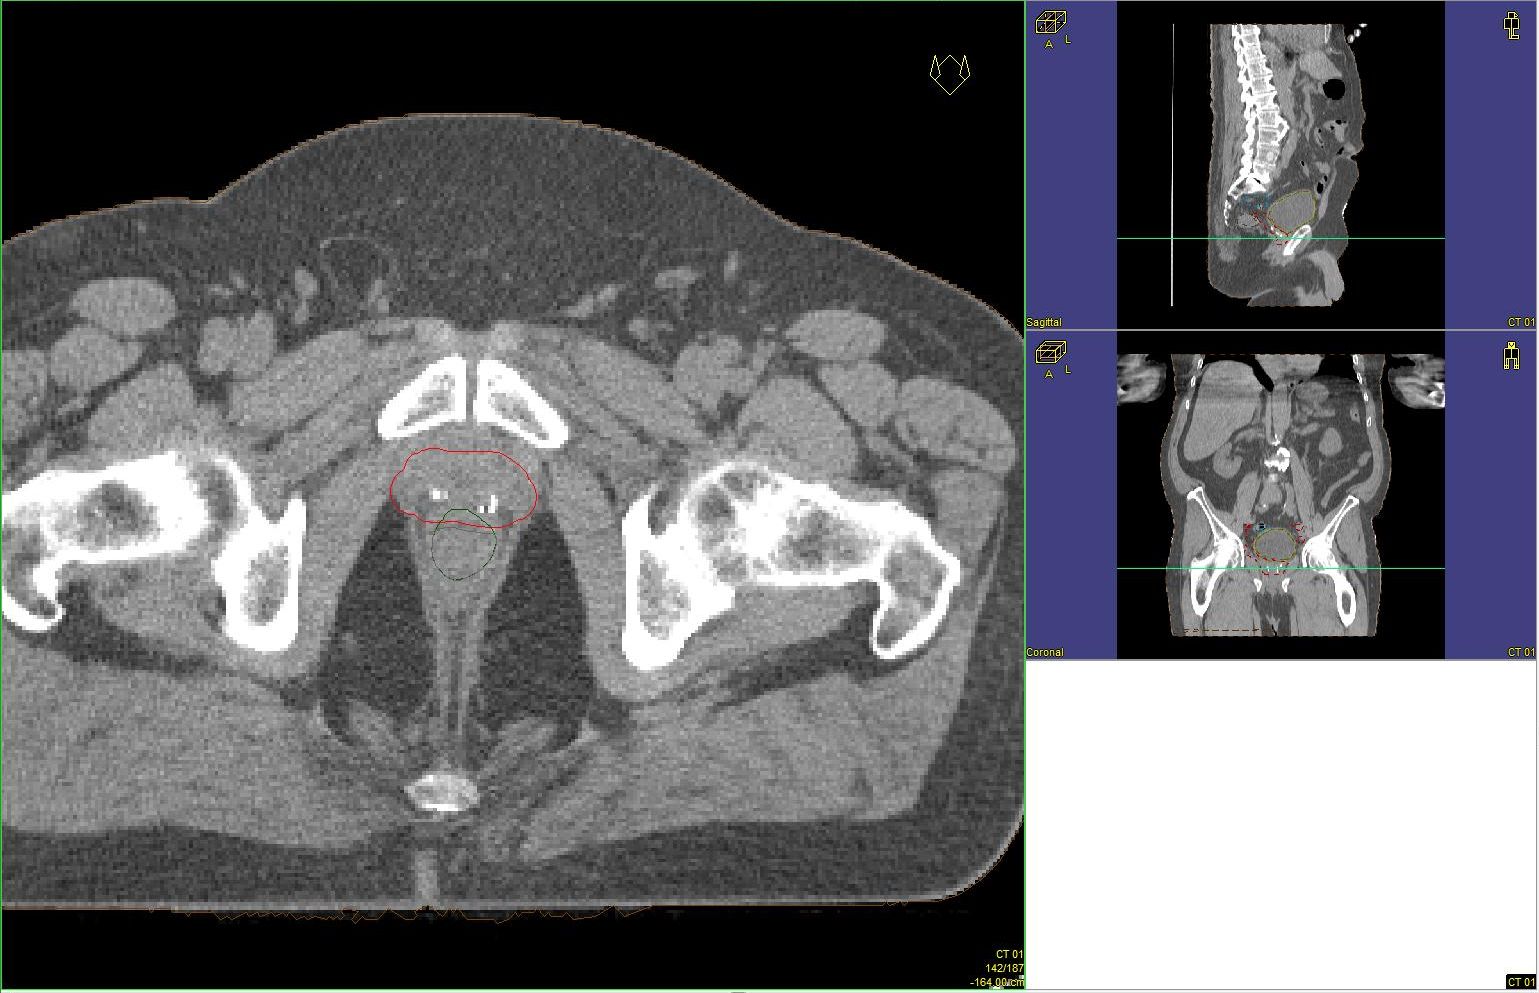

Prostata-Ca: Zielvolumen der postoperativen Radiotherapie

Beispiel: postoperative RT